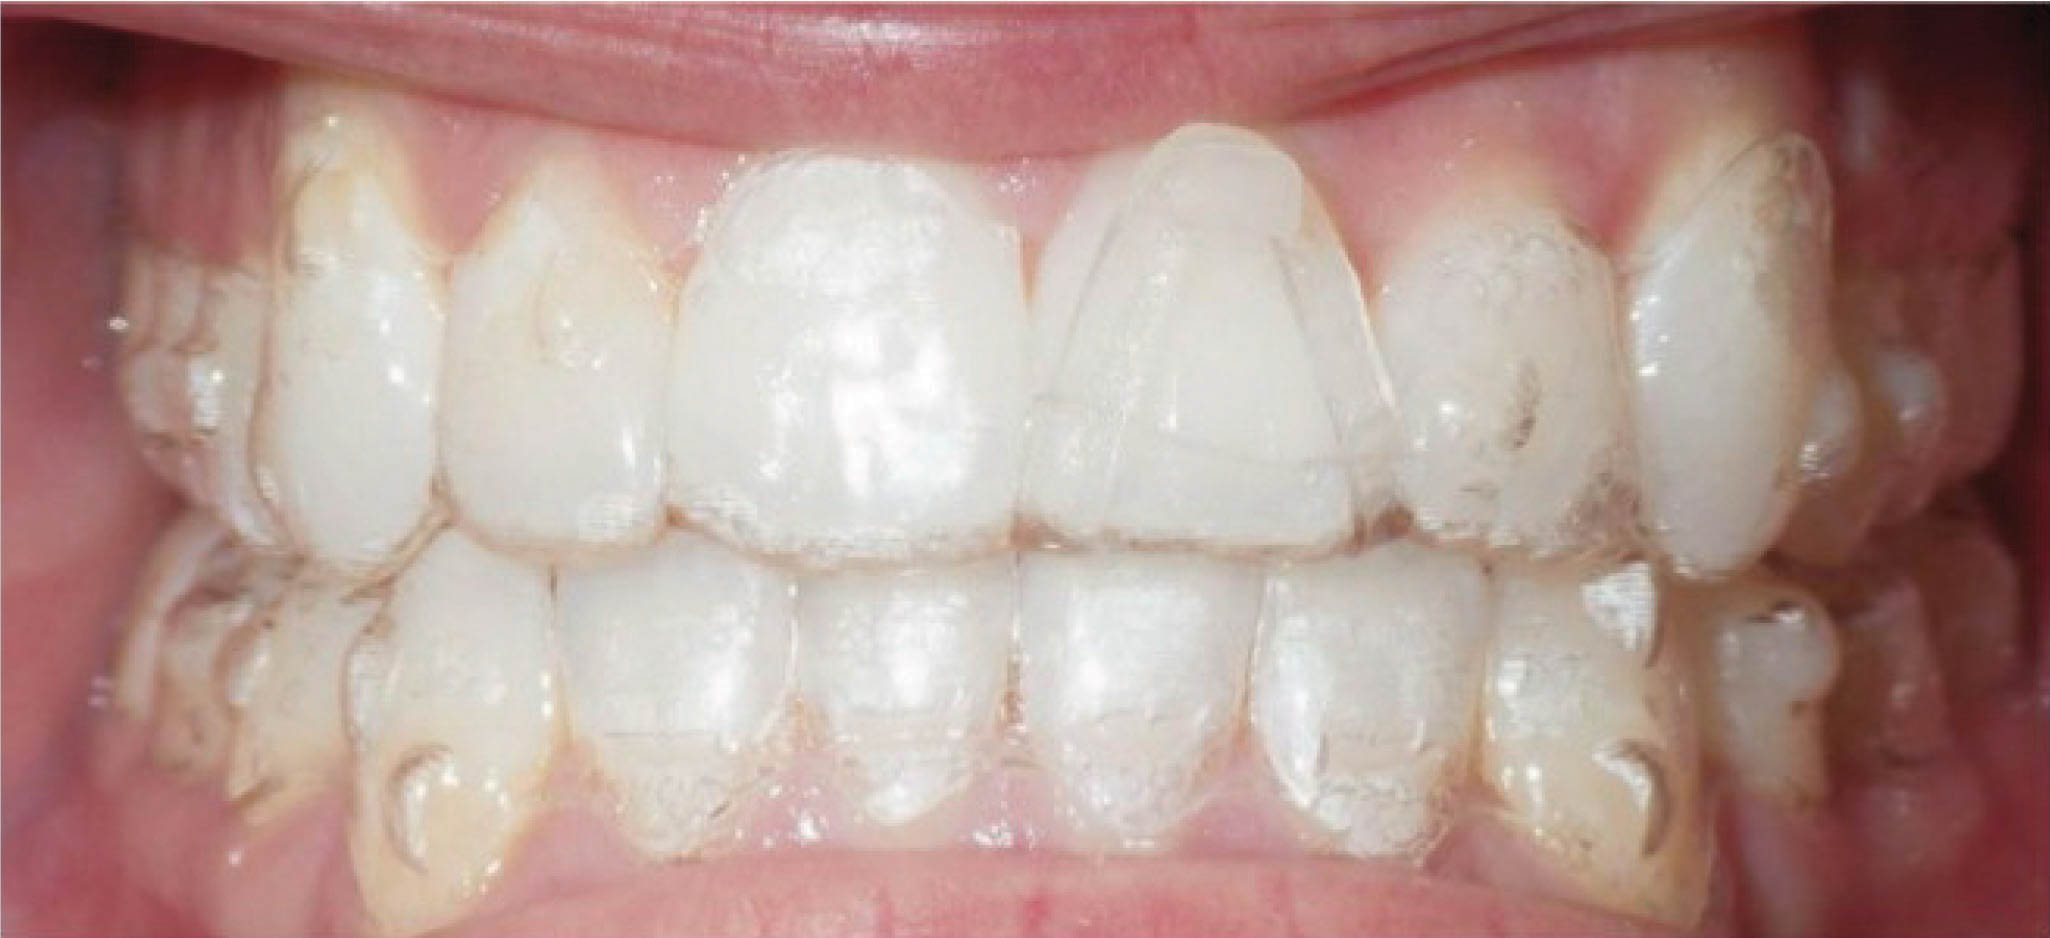

با این دستور، لابراتوار درمان اضافه روی مدل کامپیوتری انجام میدهد و اوربایت نهایی را صفر در نظر میگیرد. برای چندمین بار تکرار میکنیم که آنچه بعنوان طرح کامپیوتری میبینید، وضعیت نهایی دندانها نخواهد بود بلکه نوع اعمال نیرو برای رسیدن به یک وضعیت مطلوب است. این وضعیت مشابه همان سیم کِرودار است که وضعیت چیدمان دندانها در پایان کار نمیباشد بلکه نوع اعمال نیرو برای رسیدن به یک وضعیت مطلوب است. همانطور که در بیمار 158-6 مشاهده میکنید، در انتهای درمان کِرواسپی معکوس مشاهده نمیشود، بلکه کِرواسپی صاف و اوربایت طبیعی گشته است. در طراحی این بیمار اوربایت را صفر در نظر گرفتیم تا به اوربایت طبیعی دست پیدا کنیم.

شکل 158-6

بیمار بعدی هم همین گونه است (شکل 159-6) و 2mm اینتروژن بیشتر برای انسیزورهای بالا و پایین در نظر گرفته شده تا اوربایت صفر بشود (شکل 160-6). در پایان درمان (شکل 161-6) کرو اسپی صاف و اوربایت طبیعی گشته است و به نتایج زیبایی و فانکشنال خوبی دست پیدا نمودهایم.